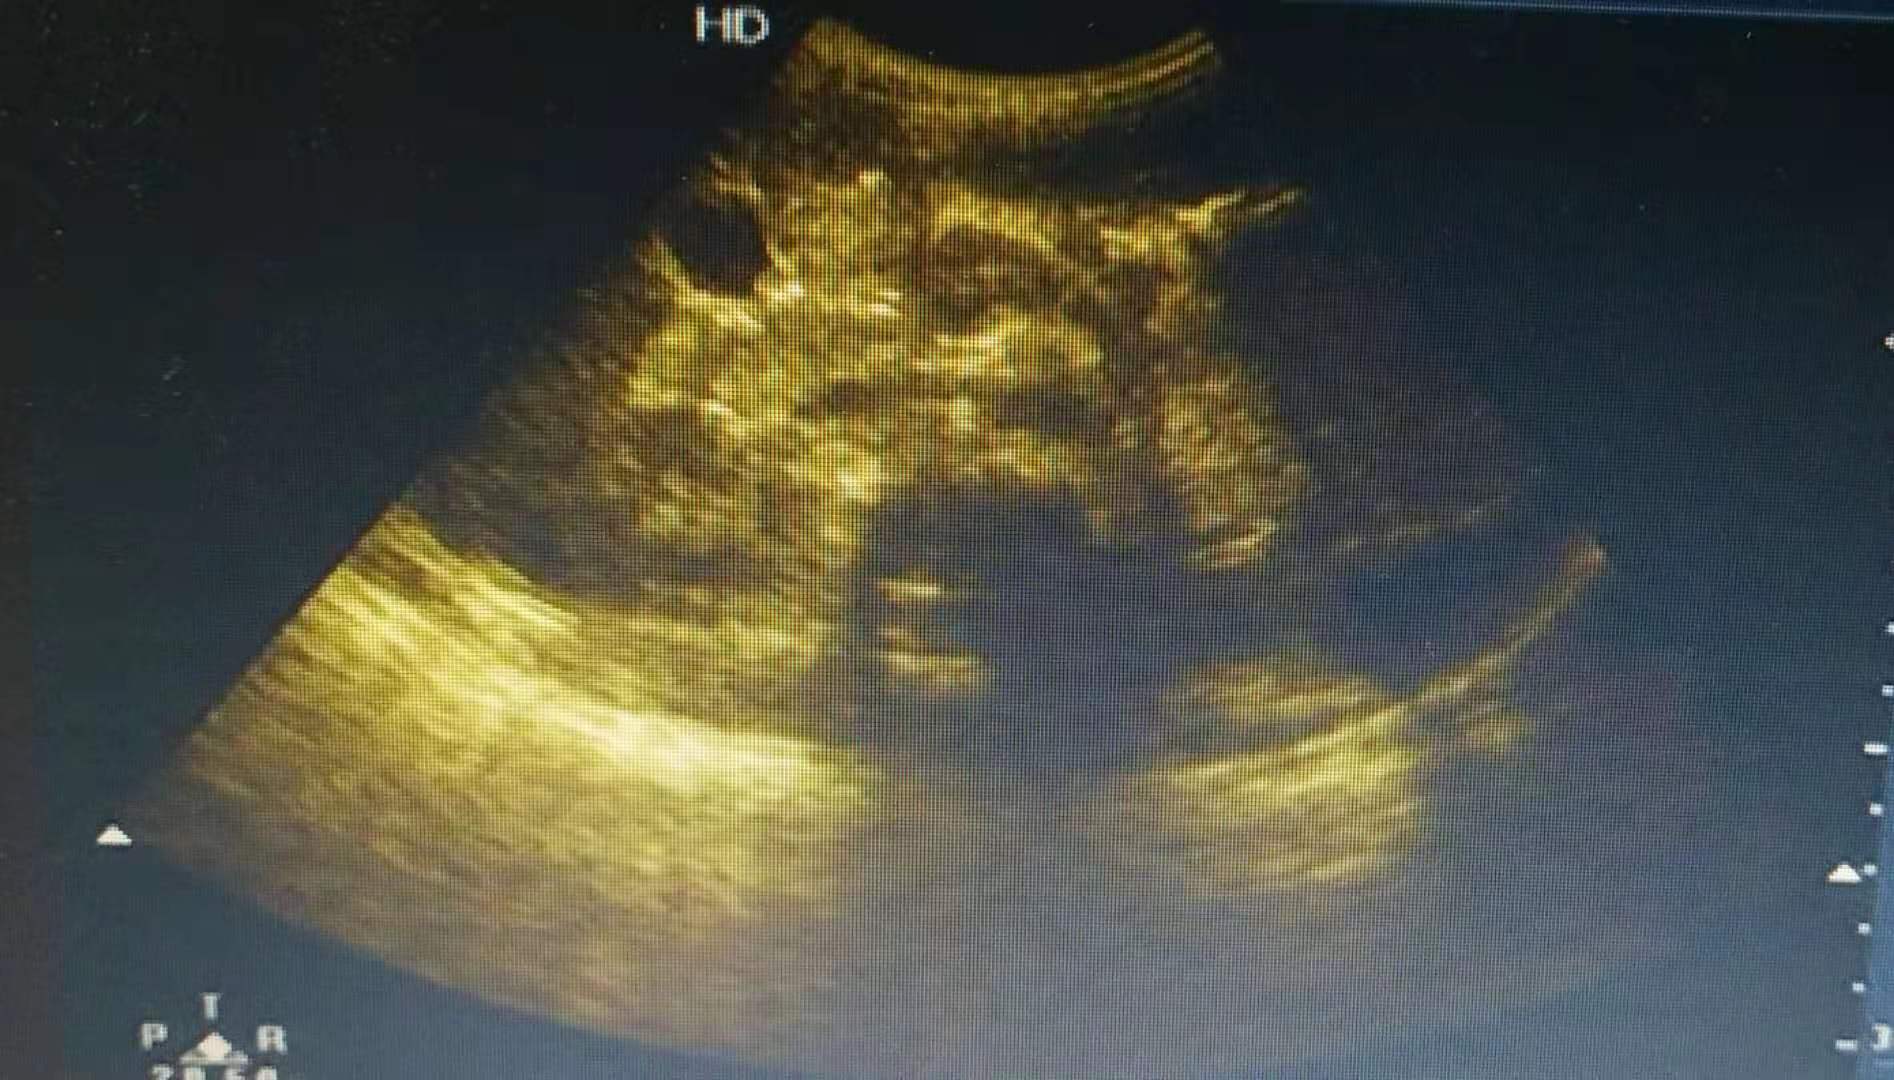

入院查体: 体温:38.5℃,脉搏:126次/分,呼吸:34次/分。Wt 15Kg。神志清楚,精神反应一般。全身皮肤未见皮疹,双侧腮部触及肿大,局部皮肤紧张,发亮但不发红,触之坚韧有弹性,有轻触痛,张口、咀嚼(尤其进酸性饮食)时刺激唾液分泌,导致疼痛加剧,双侧颈部触及数个肿大淋巴结,最大约2cmx1cm,活动可,咽无充血,颈软无抵抗,气管居中,双肺呼吸对称,胸三凹征(-),双肺呼吸音清,双侧肺未闻及干湿性啰音,心率126次/分,律齐。腹平,腹肌软,肠鸣音未见异常,4-5次/分。四肢肌力肌张力正常。 入院后完善各项相关检查,查C反应蛋白0.56mg/L,;血常规五分类:白细胞数目8.56x10^9/L,;中性粒细胞百分比44.4%;淋巴细胞百分比47.1%;彩超检查检查意见:双侧腮腺稍肿大并弥漫性改变,具有腮腺炎声像特点。双侧颈部多发肿大淋巴结声像。血淀粉酶:1013U/L,PH;肝功能、肾功能、降钙素原正常。之后我们跟家长分析孩子病情:患儿有发热,查体发现发现双侧腮部触及肿大,双侧颈部触及数个肿大淋巴结,最大约2.0cmx1.0cm,活动可,无粘连;血淀粉酶明显升高,白细胞、CRP、PCT不高,提示病毒感染,目*考前**虑诊断:流行性腮腺炎。流行性腮腺炎为自限性疾病,目前尚无抗腮腺炎特效药物,抗生素治疗无效。可予阿昔洛韦抗病毒治疗,患儿体温达38.5度以上时用布洛芬退热。由于该病有传染性,予隔离患者使之卧床休息;同时指导患儿注意口腔清洁,饮食以流质或软食为宜,避免酸性食物,保证液体摄入量。孩子由于口腔疼痛不敢吃东西,予适量补液营养支持等对症治疗。 3天后患儿无发热了,精神好,双侧面颊和颈部肿大较前消退,无咳嗽,无腹泻,吃东西也恢复到正常了,病情好转,予以办理出院。嘱继续居家隔离直至腮腺肿胀完全消退。